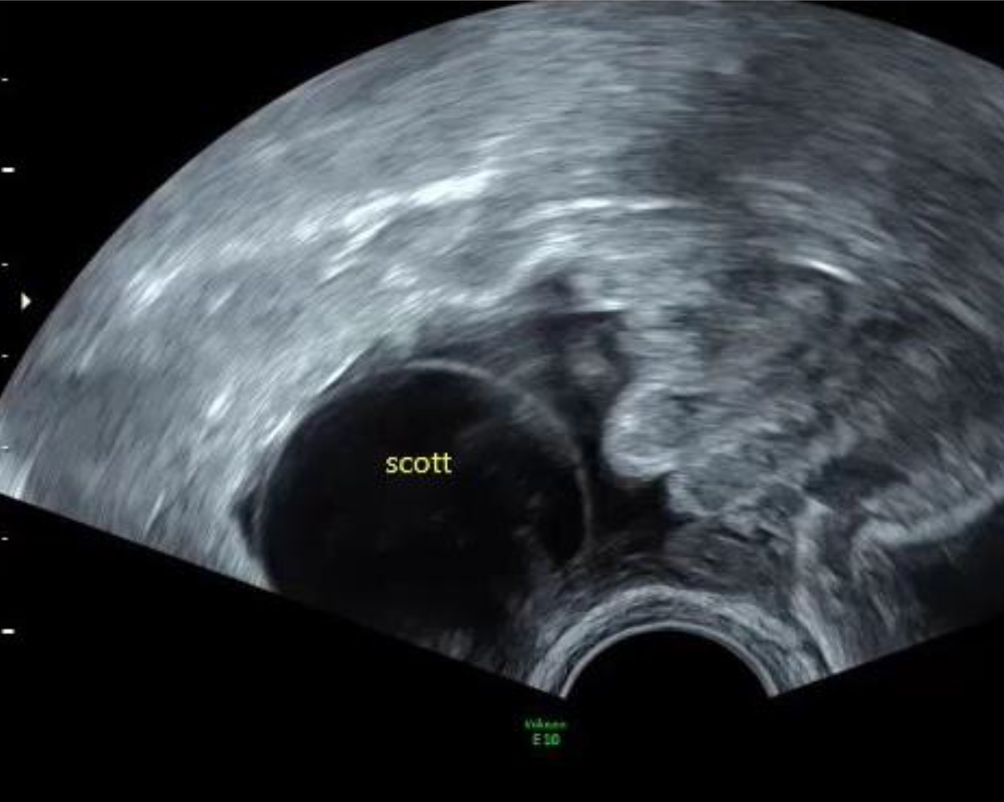

Abb. 6

Das Reservoir eines Scott-Sphinkters im Fornix vaginae. Es kann unmittelbar neben den Ovarien liegen und sollte im Zuge reproduktionsmedizinischer Maßnahmen möglichst nicht punktiert werden

Artifizielle Sphinkter für Harn- oder Stuhlinkontinenz brauchen Depots, wobei ein mit physiologischer Kochsalzlösung gefülltes Ballonreservoir auch intraabdominal in unmittelbarer Nähe der Ovarien platziert werden kann (Abb. 6). Betroffene Patientinnen wissen darüber immer Bescheid, wenn man in den Unterlagen nichts findet, sollte man sie danach fragen. Vor allem sollte ein voreiliges Anpunktieren dieser Ballonreservoirs, sei es aus diagnostischen Gründen, sei es, weil man es für einen Follikel hält, unterbleiben. Rücksprache mit Vertretern des Fachs (meist Chirurgen und Urologen), die üblicherweise solche Implantate legen, kann sehr aufschlussreich sein und Schaden für die Patientin verhindern [9].